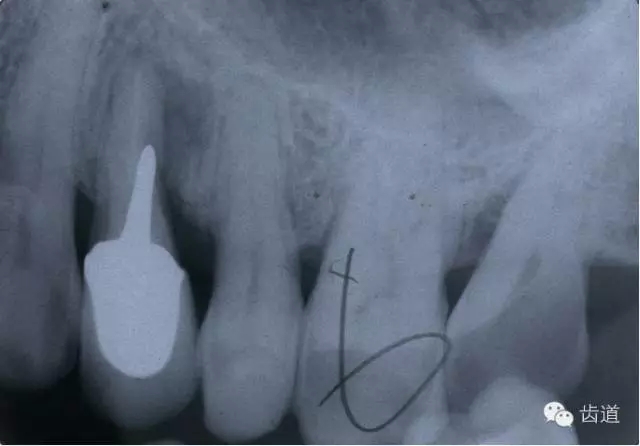

左上4鑄造樁側(cè)穿

左上7近中頰根器械折斷

右上6腭根器械折斷